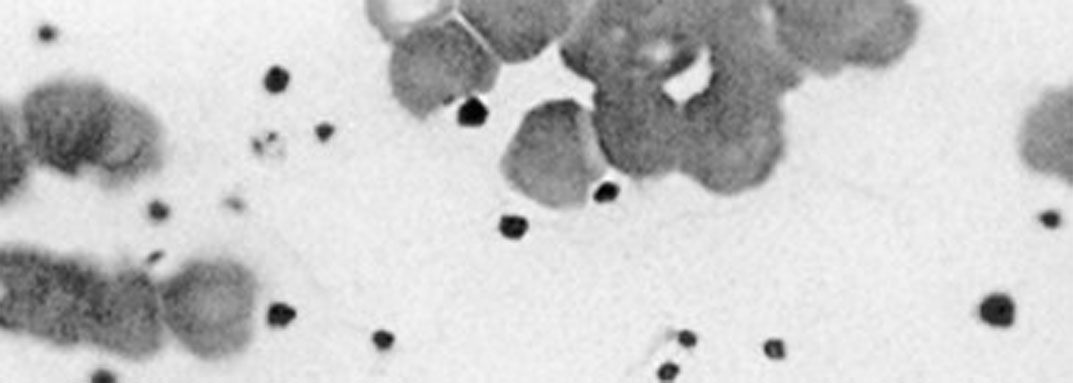

GSC Stem Cell Therapy VS General PRP

GSC Stem Cell Therapy

4 to 6x more stem cells

A high survival rate of 80-98%

Stable CLOSED SYSTEM

Rich

VS

Standard

Concentration

Survival Rate

Stability

Stem cells

General PRP

Only the platelet count doubled

A survival rate reaching 50%

OPEN SYSTEM

Insufficient